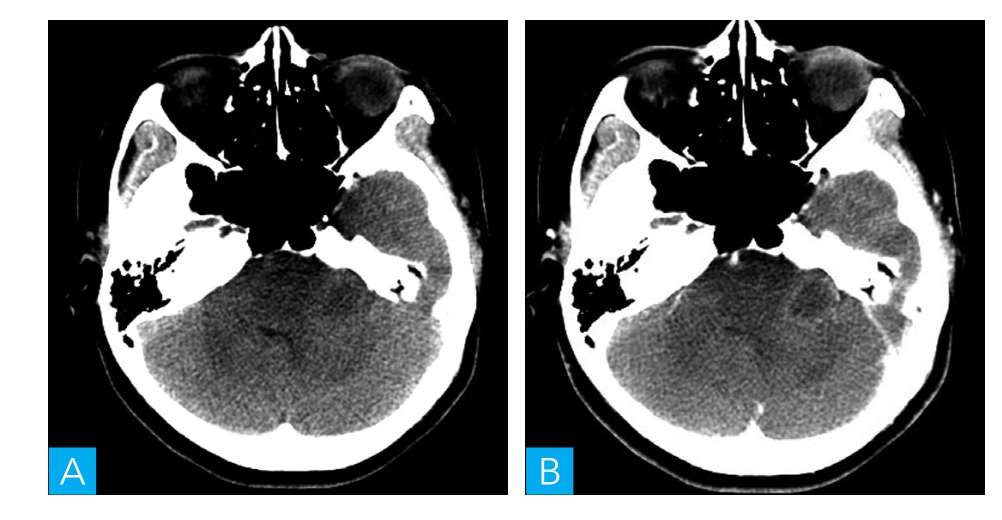

图1-1-1 乳突CT扫描

A.轴位CT平扫;B.轴位CT增强

病人为青年女性,慢性起病,临床表现为头晕、复视、左耳听力下降、面部发麻。CT表现为左侧桥小脑角区域稍低密度占位病变,病灶内未见钙化及出血改变,增强扫描呈环形强化,邻近内听道未见增宽,颅底骨质未见增生或破坏改变。MRI表现为左侧桥小脑角区域肿物,边缘呈等T1、稍长T2信号,中央区可见液化坏死,增强扫描呈明显环形强化,与脑组织分界不清,邻近脑干及左侧小脑可见大片水肿信号影,左侧面听神经未见增粗及强化,左侧内听道未见增宽、四脑室稍受压变窄。根据以上特点,该病变定位于脑内,考虑为弥漫性星形细胞瘤。

本病例为青年女性,慢性起病,病灶位于左侧桥小脑角区,CT表现为稍低密度肿块,病灶内见更低密度区,病灶内未见钙化及出血改变,增强扫描呈环形强化,邻近内听道未见增宽,颅底骨质未见增生或破坏改变;MRI上表现为左侧桥小脑角区肿物,病灶内可见液化改变,边缘呈等T1稍长T2信号,病灶与脑组织分界不清,增强扫描呈明显环形强化,邻近脑干及左侧小脑可见大片水肿信号影,左侧面听神经未见增粗及强化,左侧内听道未见增宽、第四脑室稍受压变窄。根据以上特点,考虑为弥漫性星形细胞瘤。该病发生在桥小脑角区域,需要与听神经瘤、脑膜瘤、表皮样囊肿相鉴别。仔细观察肿瘤密度或信号特点,与周围脑膜关系,邻近听神经及内听道是否改变,颅骨骨质有无异常等情况则不难鉴别。